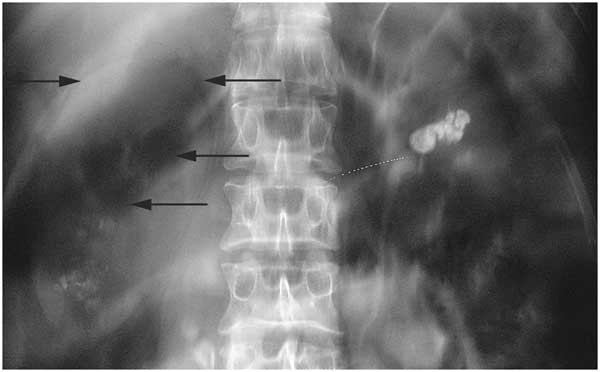

췌장은 소화와 혈당 조절에 핵심적인 역할을 하는 장기로, 위치가 비교적 깊어 통증 양상이 모호하게 느껴질 수 있습니다.

일반적으로 췌장은 위의 뒤쪽, 복부 중앙에서 약간 왼쪽에 자리하고 있으며, 길쭉한 형태로 십이지장부터 비장 쪽으로 뻗어 있습니다. 하지만 통증은 췌장 자체 위치보다 신경 분포와 연관되어 등이나 옆구리로 전달되는 경우가 많아, 환자 스스로 정확한 위치를 짚기 어렵습니다.

췌장의 해부학적 위치 정리

췌장은 상복부 깊숙한 곳에 위치해 있으며, 앞쪽에는 위가 있고 뒤쪽에는 척추가 자리합니다. 이 때문에 췌장에 염증이나 압력이 생기면 통증 신호가 척추를 따라 등으로 전달됩니다. 통증이 중앙 등이나 오른쪽 등으로 느껴질 수 있어 허리 통증으로 오인하는 사례도 적지 않습니다.